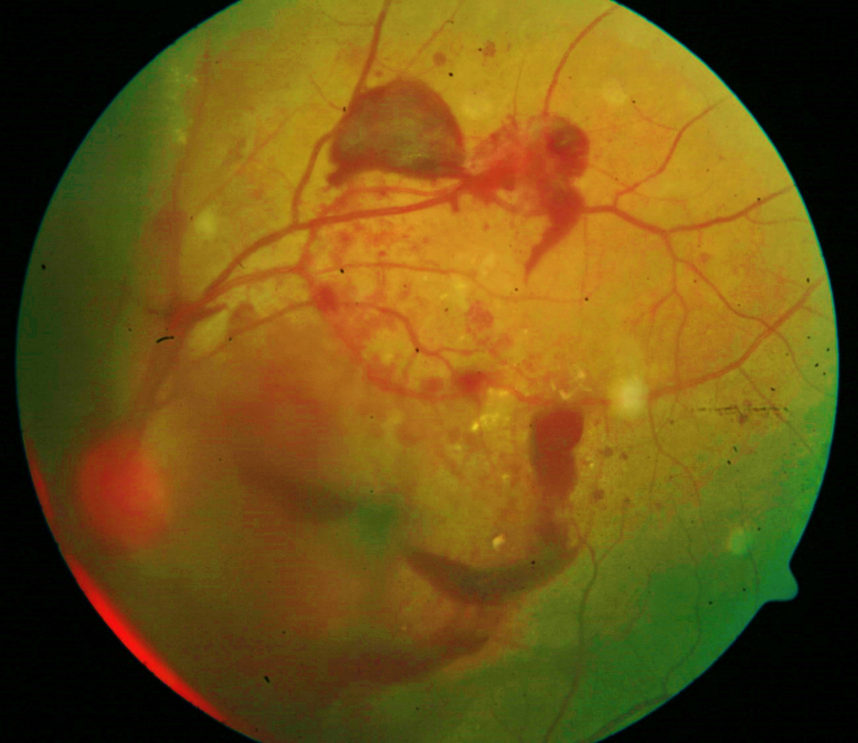

Retinopatia proliferativa grave com hemorragia intravítrea